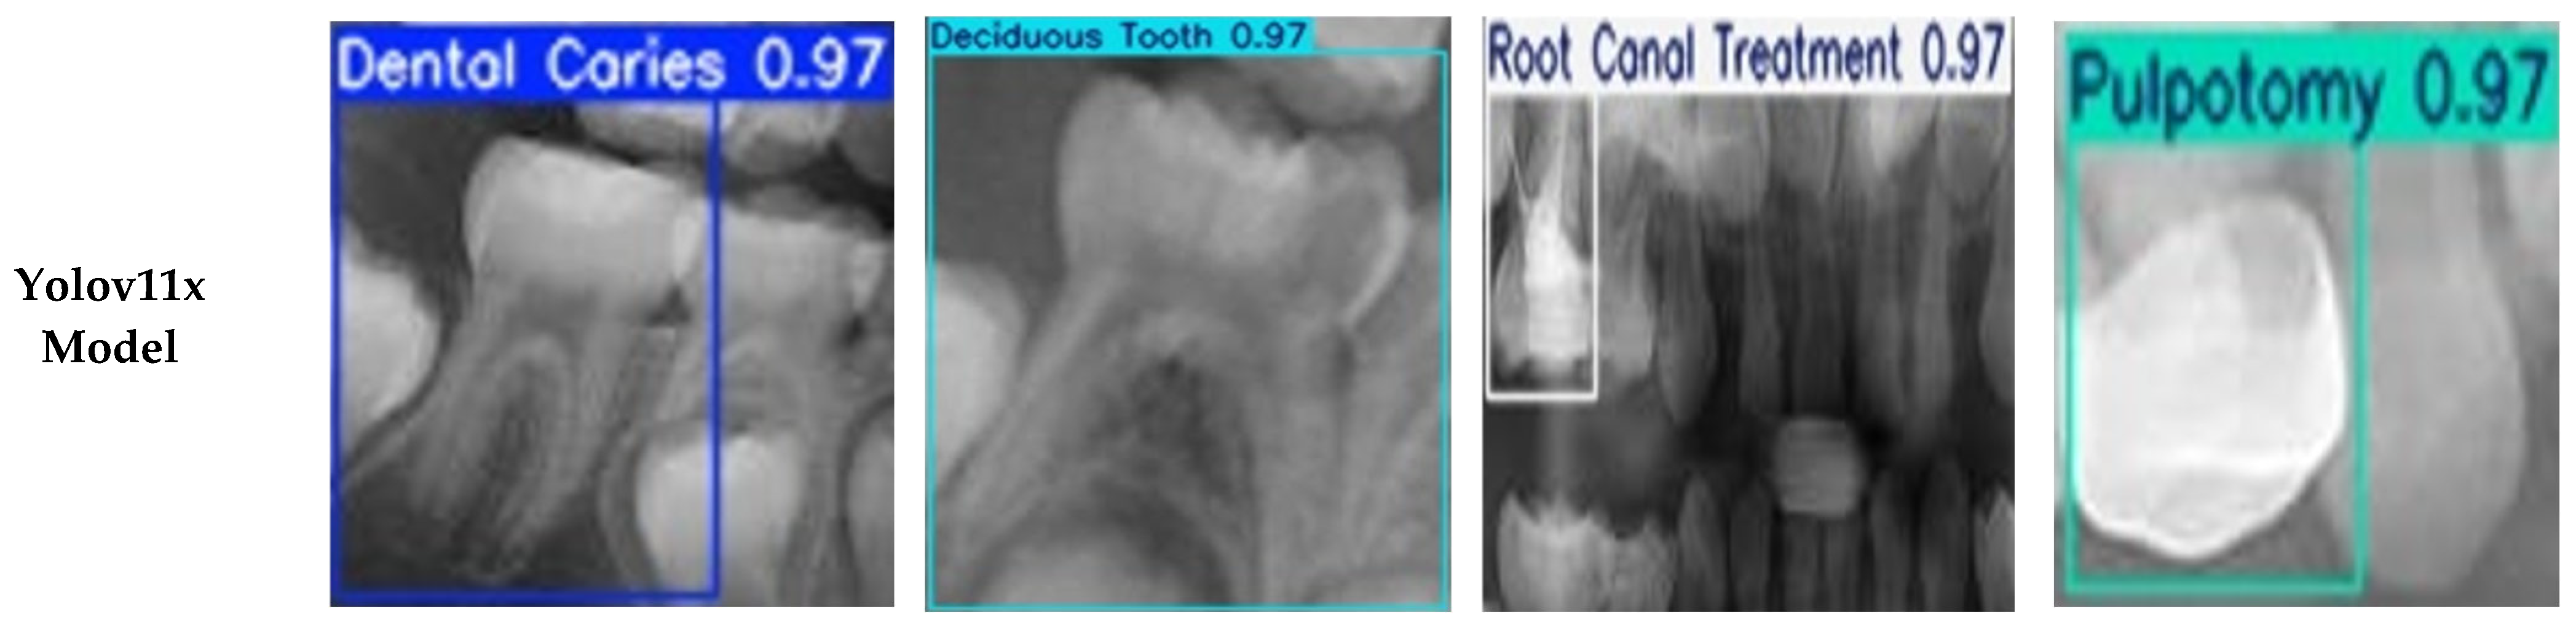

| Dental Caries | 830 | 43.57 | 43.57 |

| Deciduous Tooth | 791 | 41.52 | 85.09 |

| Root Canal Treatment | 171 | 8.98 | 94.07 |

| Pulpotomy | 113 | 5.93 | 100.00 |